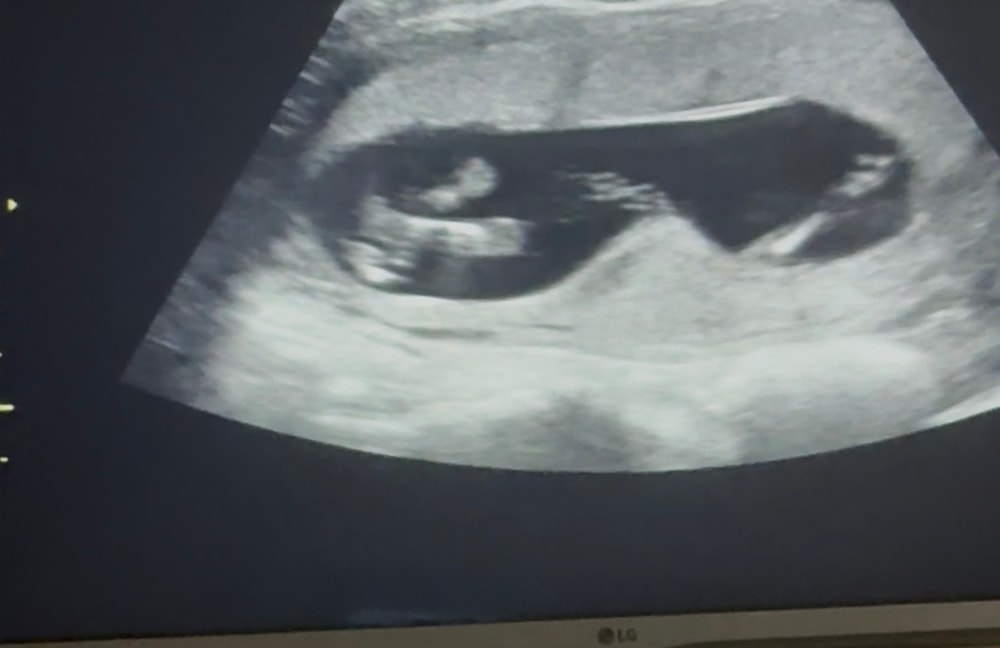

Я вас может успокою, но где я живу даже такого термина нет. Сокращение матки, как мышечного органа, без сильной схвактообразной боли и выделений считается нормой. И все ок, все ходят:) По картинке ничего ужасного, это же проекция, нигде там малыша не зажало